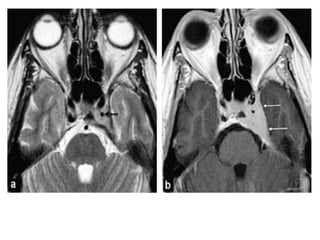

• #14 Venous thrombosis: bilaterally heterogeneous and enlarged cavernous sinus on T2-wi (a), containing low signal areas on enhanced T1-wi suggesting clots (blacks arrows: b).